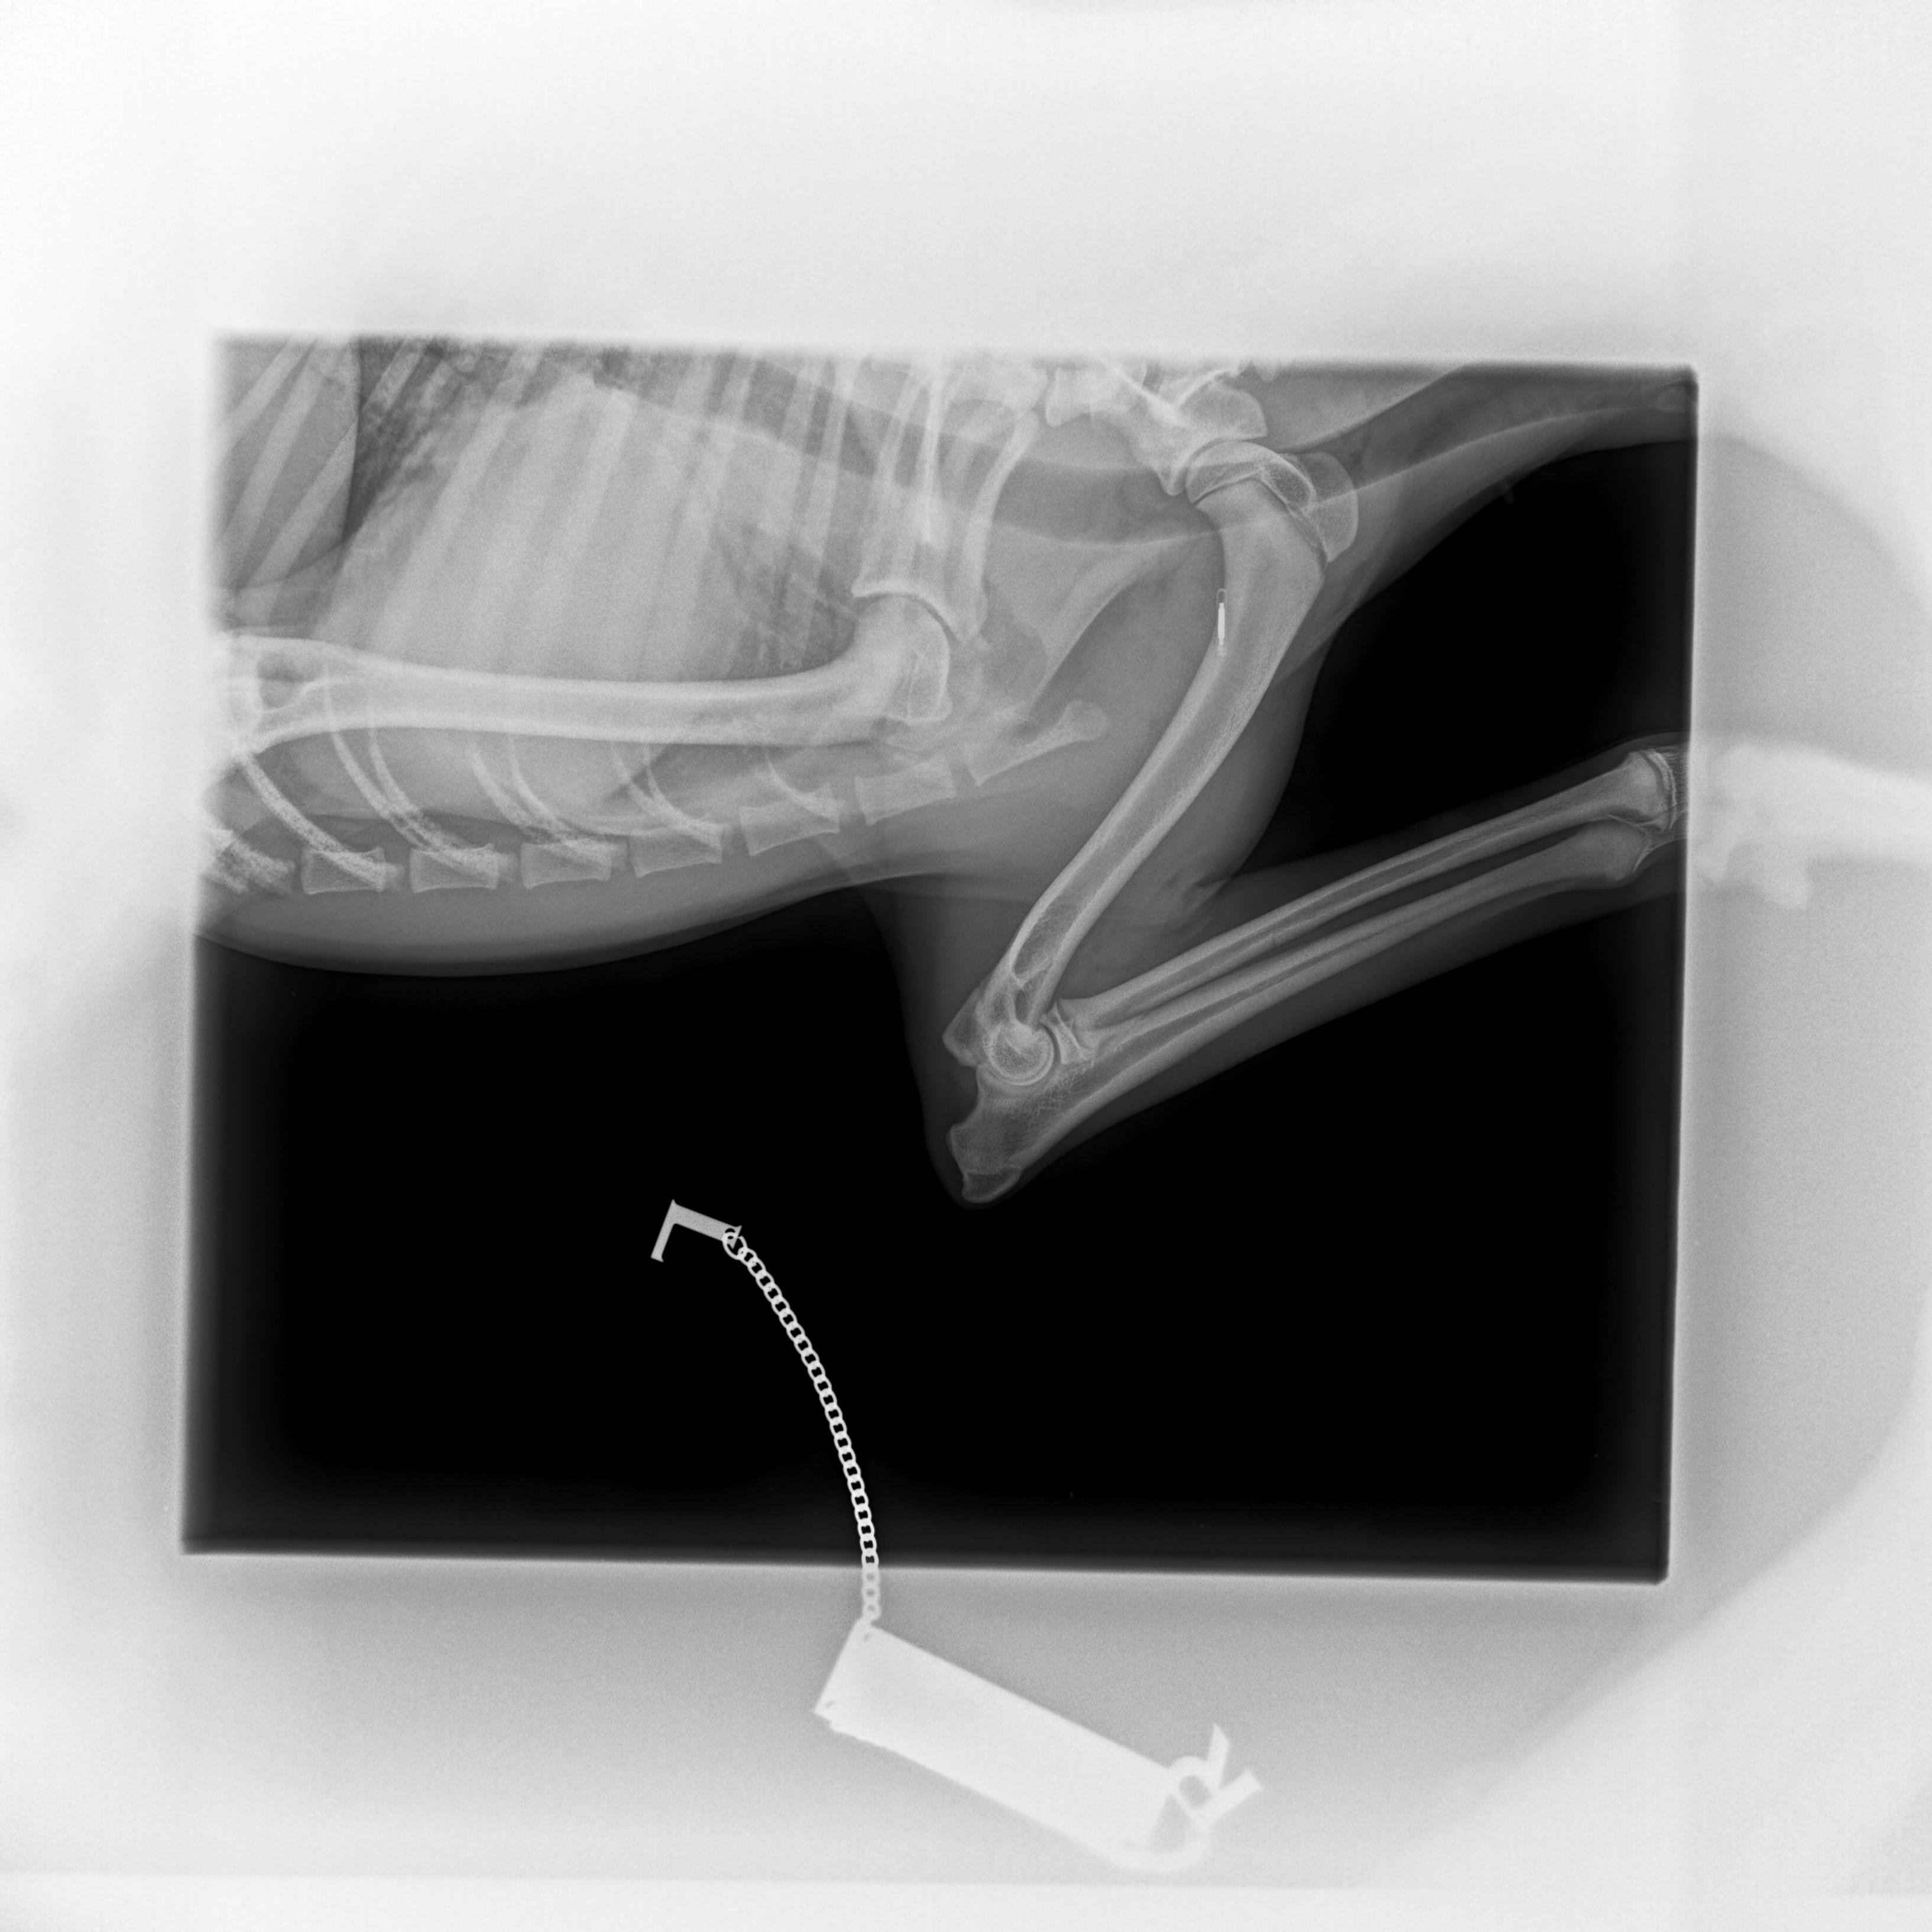

Cushingův syndrom, taktéž nazývaný Hyperadrenokorticismus, patří v současnosti spolu s diabetes mellitus mezi nejčastěji se vyskytující endokrinologická onemocnění psů. Způsobuje ho nadbytek glukokortikoidů, jako Cushingův syndrom pak označujeme soubor příznaků, které onemocnění doprovázejí.